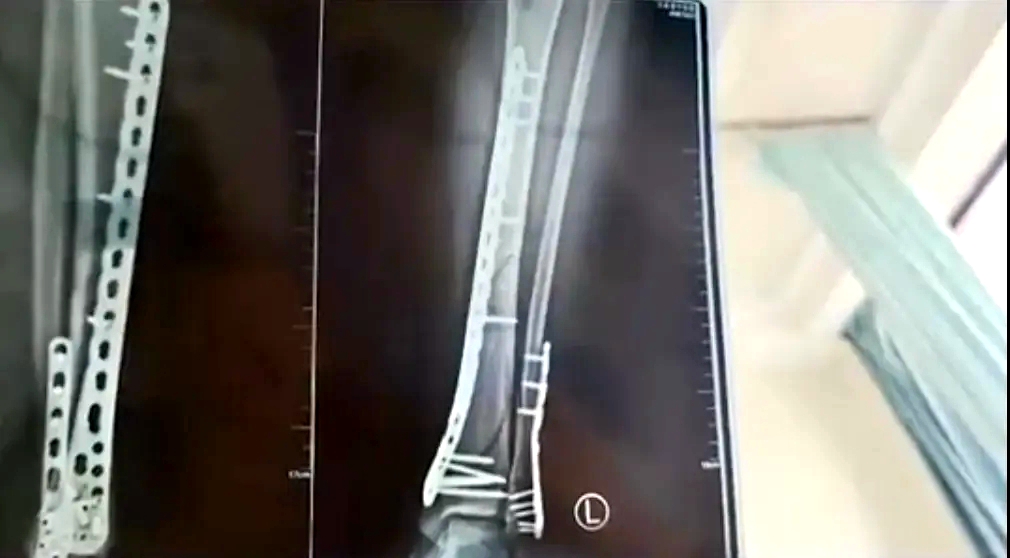

女子穿7cm厚洞洞鞋崴腳

致左腿粉碎性骨折

近日,甘肅蘭州的武女士稱母親節(jié)當(dāng)天,自己穿7cm厚洞洞鞋下樓,不慎崴腳摔倒,致使左腿粉碎性骨折。

武女士稱:因?yàn)槎炊葱男妆容^厚,腳掌中間又是凹進(jìn)去的,自己下樓梯的時(shí)候,正好踩到凹進(jìn)去的地方,當(dāng)時(shí)腳沒有踩穩(wěn),整個(gè)人的重心往前撲,所有重力都集中在腿上,結(jié)果就骨折了。

該女子稱,目前已做完手術(shù)在家休養(yǎng),不過下地得拄拐才行,且下地有時(shí)間限制,不能久站,而骨折完全康復(fù)可能需要3個(gè)月,她提醒大家穿增高鞋要注意。